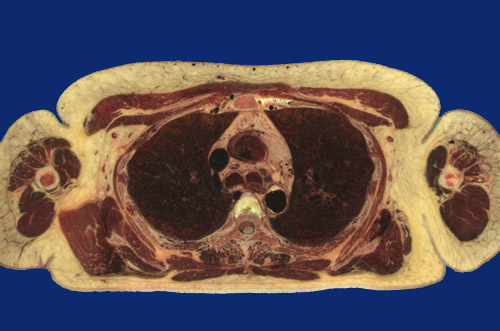

Identify the following regions in the image above: Pectoralis major - Pectoralis minor - Deltoid - Humerus - Teres minor - Scapula - Infraspinatus - Subscapularis - Serratus anterior - Rhomboid major - Intercostal m. - Erector spinae groups (Transversospinalis m) - Trapezius - Sternum - Anterior mediastinum (Thymus) - Pulmonic trunk - Trachea - Esophagus - Aorta, lower arch - Vertebral body - Spinal cord - Right upper lobe - Left upper lobe